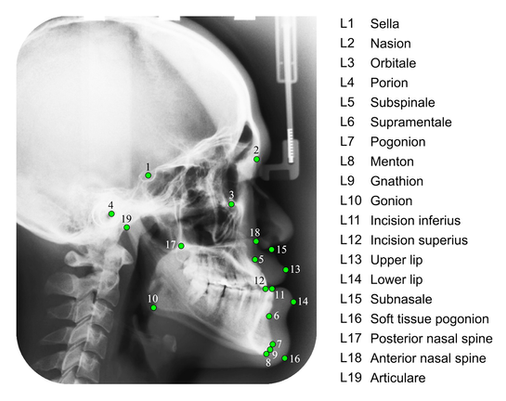

Ceph Analyses

Alternatively, if it's a full tracing and analysis of your patient's x-ray, we can provide you with several different cephalometric analyses and diagrams.